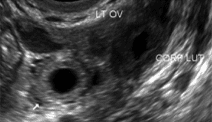

Adnexa beskrives mhp ekstrauterin graviditet, såfremt der ikke findes sikker intrauterin gestationssæk. Er corpus luteum til stede?

Blommesæk (BS):

Blommesækken ligger i gestationssækken og ses som en sfærisk struktur med ekkotom opklaring.

BS forsvinder ofte efter 10. uge.

Tilstedeværelse af BS konfirmerer intrauterin graviditet.

BS konstateres fra 38-40 dag (uge 5+3-5+5).